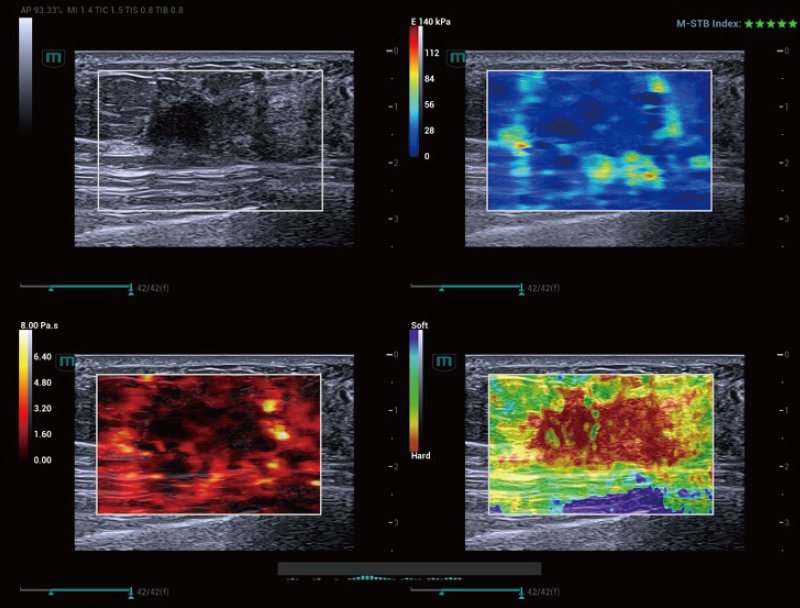

STVi maakt de kwantitatieve evaluatie van weefselviscositeit mogelijk en biedt realtime, multi-parametrische beeldvorming. Dit maakt een bredere benadering mogelijk van beeldvormingsdiagnose en kwantitatieve analyse van chronische leverziekten, borstlaesies en andere aandoeningen.

Dubbele kwantitatieve co?ffici?nten

Beoordeling van chronische leveraandoeningen

Meerdere kwantificeringstools

Beoordeling van borsttumoren